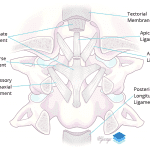

- Multiple tiny acute displaced fractures along the anterior aspects of both C1 superior articular facets with mild anterior subluxation of the occipital condyles relative to C1 and widening of the posterior aspect of both atlanto-occipital joints

- Widening of the C1-C2 interspinous interval and of the superior aspect of the sagittal atlantodental interval

Acute fracture-subluxation at the craniocervical junction with multiple tiny acute displaced fractures along the anterior aspects of both C1 superior articular facets, mild anterior subluxation of the occipital condyles relative to C1, widening of the posterior aspect of both atlanto-occipital joints, widening of the C1-C2 interspinous interval, and widening of the superior aspect of the sagittal atlantodental interval. MRI could further evaluate the extent of ligamentous injury.